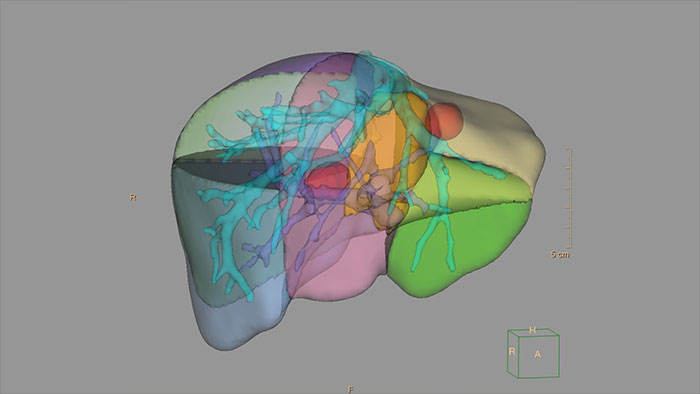

- 3D Modeling

-

3D Modeling

Streamlined modeling workflow

Allows to view volumetric images of anatomical structures, perform segmentation, edit and combine segmented elements (tissues) into a 3D model.

Benefits

- Studies of CT & MR can be used for creating a single 3D model of the same patient. The application provides tools that allow the user to align between the volumes of interest in the images.

- 3D Modeling batches files can be easily exported in standard formats such as STL, with the option to also provide a 3D PDF as an additional means for results sharing with 3D printing or other services* .

- The user may determine the information related to the exported elements of the 3D model such as smoothness and output mesh size.

- Contours can also be exported as RT Structures.

*3D models are not intended for diagnostic use.